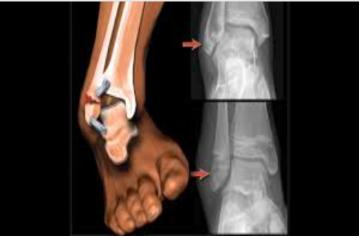

A그림을 보시면 종아리뼈가 더 길고 아래로 내려와 있으며 정강뼈는 종아리뼈보다 위쪽에 위치하는 것을 볼 수 있습니다. 발목을 만져보셔도 알겠지만 안쪽 복숭아뼈보다 바깥쪽 복숭아뼈가 더 아래로 내려와 있습니다.

이러한 뼈의 구조로 인하여 바깥쪽으로의 꺽임(eversion)보다 안쪽으로의 꺽임(inversion)이 가동범위가 더 크게 일어납니다.

발목관절에 붙어있는 발의 인대는 그림과 같이 안쪽면에는 세모인대가 가쪽면에는 앞목말종아리인대, 발꿈치종아리인대, 뒤목말종아리인대 가 발목의 뼈들을 단단히잡아주고 있습니다. 안쪽면에 있는 세모인대가 가쪽면에 붙어 있는 인대보다 두꺼운 것을 볼 수 있습니다.

뼈의 구조와 인대 두께를 보면 왜 안쪽들림 손상(염좌) 가 빈번하게 발생하는지 아시겠죠?

뼈의 구조에 의해서 안쪽들림(inversion) 가동범위가 큰데 뼈와 뼈를 잡아주는 인대마저 안쪽보다 얇으니 손상을 자주 당할 수밖에 없는 구조인거죠.